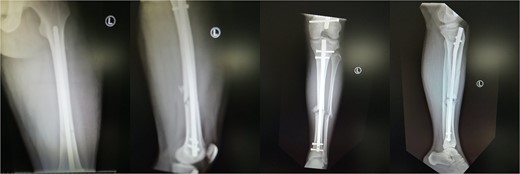

Upon suspicion, the patient should be transferred to the operating room, where either selected or extended fasciotomies should be performed. Upon early diagnosis and emergent reaction, the prognosis of WLCS is excellent with 95% of patients reporting no significant deficit [7,9]. On the other hand. Fitzgerald et al. [10] reported that 81% of patients undergoing fasciotomies develop long-term complications, but this should not deter surgeons from performing fasciotomies when deemed necessary. In the setting though of a delayed diagnosis, like our second case, surgical fasciotomy is no longer effective and might lead to serious complications, such as infection and limb amputation [11]. Our review suggests that the 29.4% of the patients who develop WLCS post-surgery achieved full recovery. 5.9 and 64.7% of the patients achieved no and partial recovery, respectively (Fig. 4).

4. Chrysostomos Tsatsoulas. Figure formatting, writing of Figure 4.